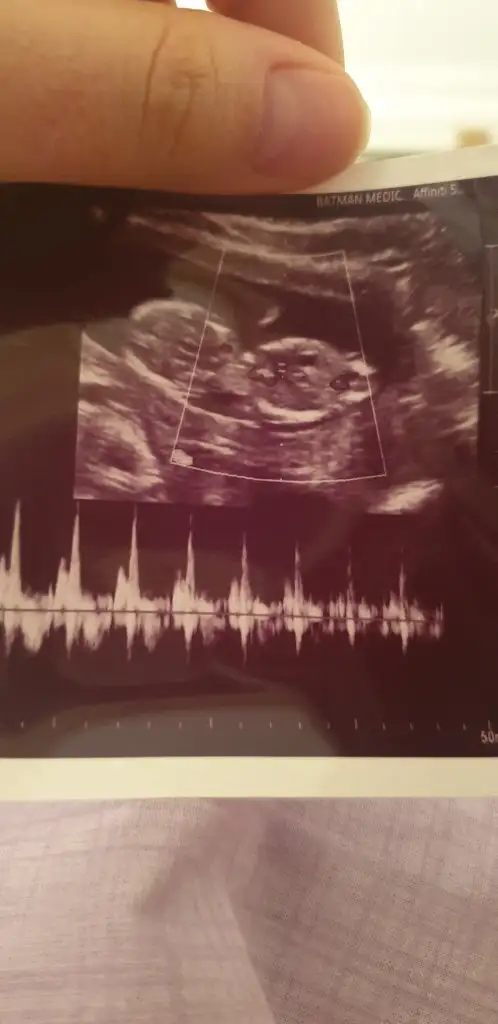

Arkadaşlar rica etsem bana da bakar mısınız doktor söylemedi henüz

Kaç haftalık sanki kız gibi bacagı kapatmış nubu tam göremesemde gibi gibi ekleyerek kız diyorum 11 yada 12 hafta olmalı 😊